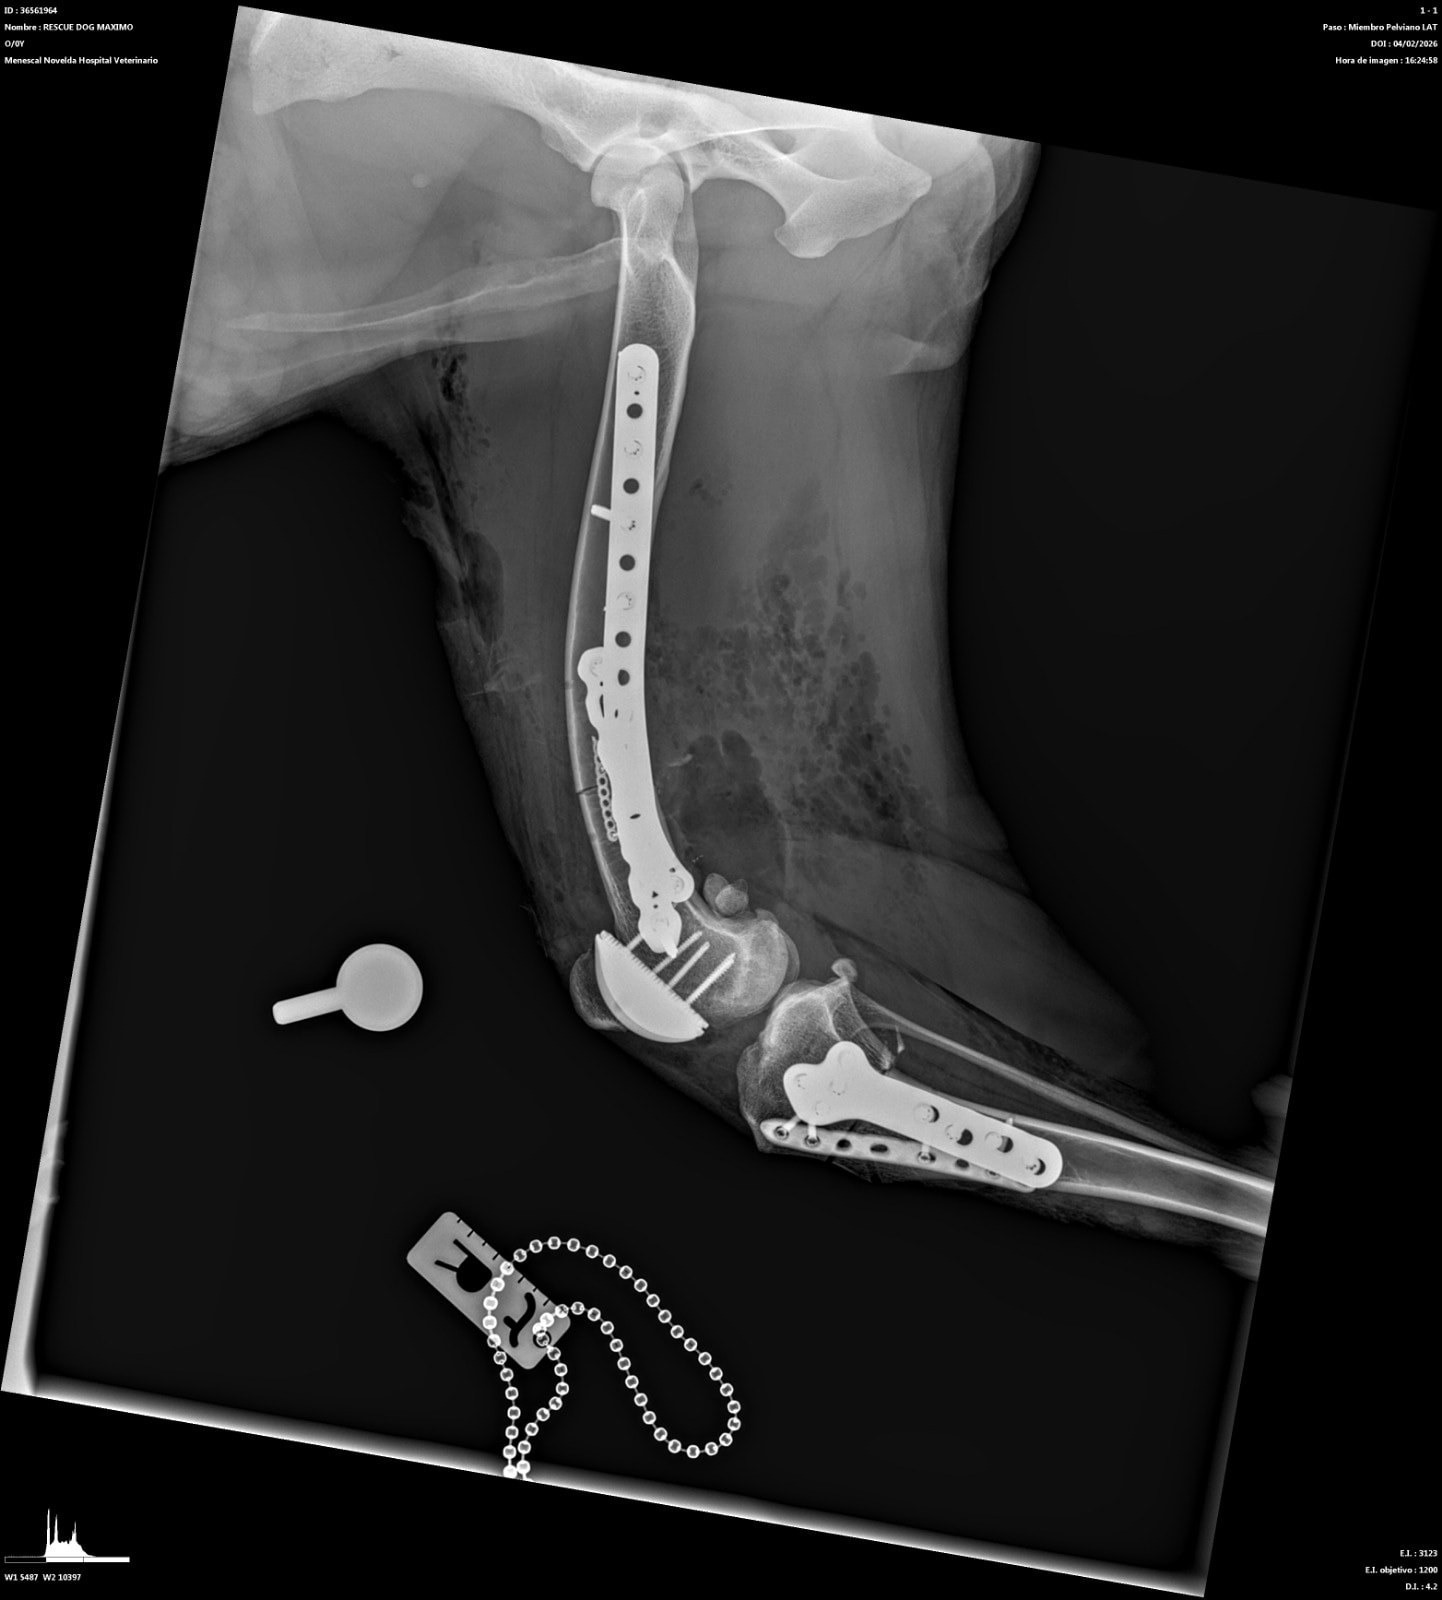

Abbiamo allegato fattura e lastre post-operatorie in totale trasparenza

CANGU è uno dei nostri grandi combattenti. Lo abbiamo salvato in Spagna molto tempo fa, quando viveva in condizioni disperate: grave dolore e difficoltà nei movimenti, zero prospettive senza un intervento immediato. Da allora abbiamo fatto tutto ciò che era possibile per offrirgli una vita degna. Abbiamo già finanziato due interventi complessi al primo arto posteriore:

– il primo intervento purtroppo non ha portato alcun miglioramento;

– il secondo, una protesi totale del ginocchio, ha finalmente dato risultati positivi e oggi quell’arto gli permette una migliore stabilità.

Ora ci troviamo di fronte ad passo indispensabile per garantirgli una qualità di vita accettabile: intervenire sul secondo arto posteriore, ancora in condizioni critiche. Lasciarlo così significherebbe condannarlo a un dolore costante, a un peggioramento progressivo con un carico eccessivo sulla prima protesi e a una vita senza autonomia. Operarlo, invece, significa dargli una possibilità reale di camminare meglio, di muoversi, di vivere dignitosamente. L’intervento previsto è un DFO con la protesi completa del secondo ginocchio. Il costo è di 8.098 euro (allegato preventivo). Non otterremo un cane “perfetto”: Cangu avrà comunque dei limiti, perché per un recupero totale servirebbero protesi anche a livello delle anche. Ma questo intervento rappresenta la parte fondamentale del suo percorso di riabilitazione, quella che può migliorare la sua quotidianità.